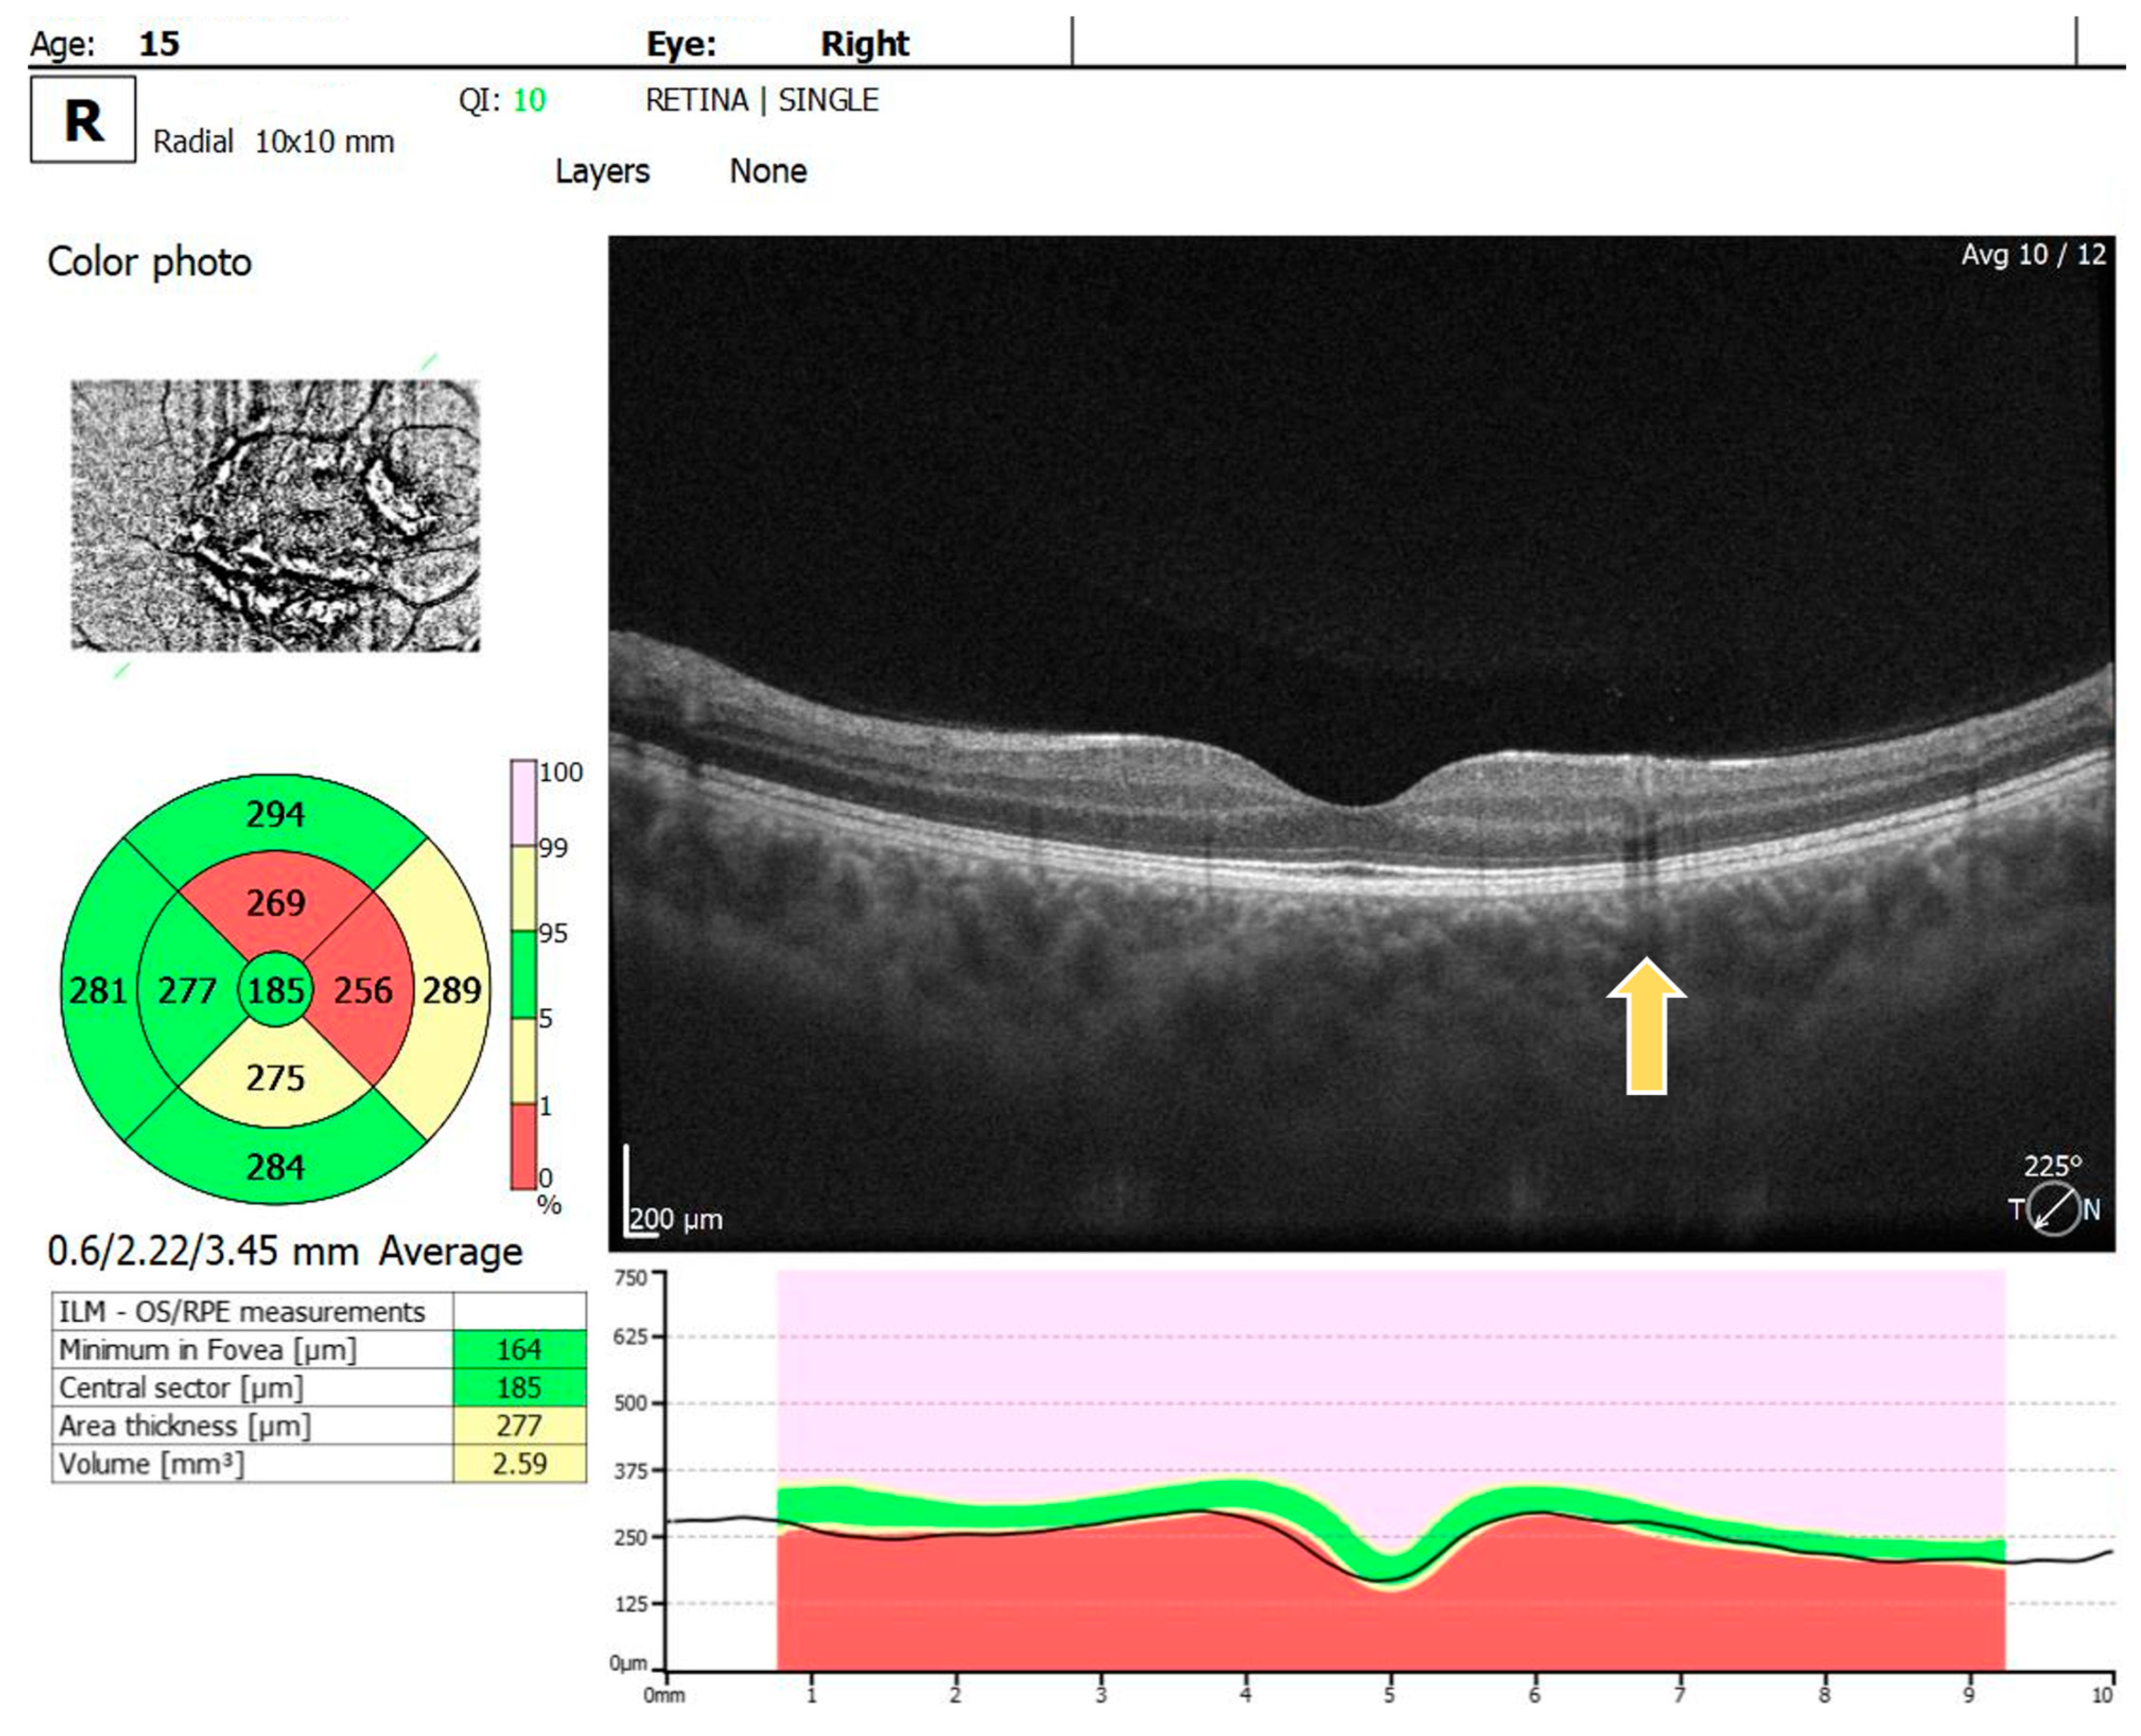

2. Case Report